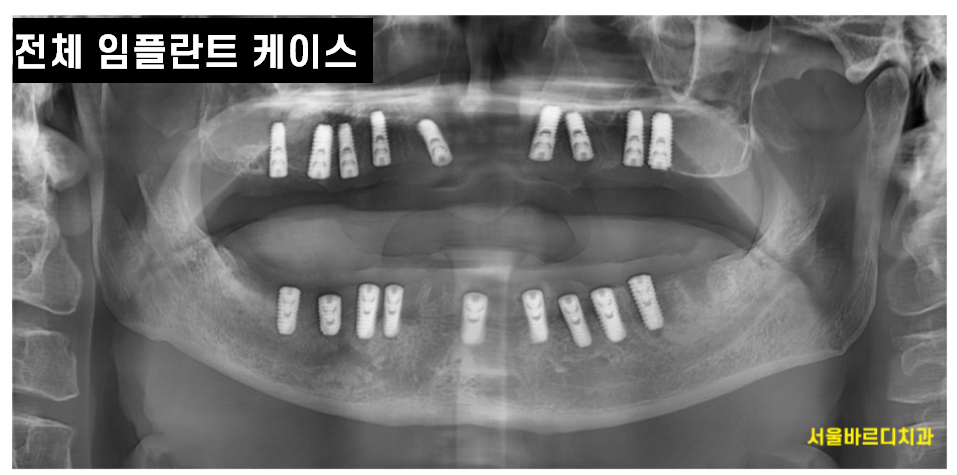

세번째 치아가 많이 없어 식사가 어려울 때

전악 치료가 필요한 환자들에게는

임플란트 임시틀니 필수입니다.

위의 케이스같은 환자분들은

풍산동 임플란트 치료 시 임시틀니 생존을 위해 필요합니다.

완성을 위해 몇개월이 소요되는데

그대로 둘 수는 없으니까요ㅠ